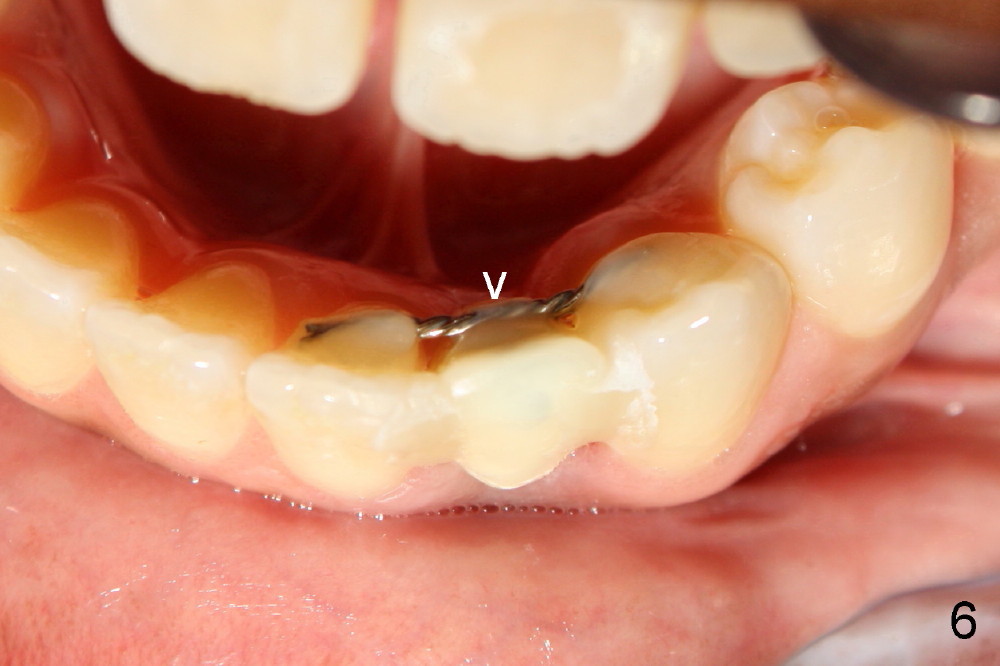

Informed consent is obtained with emphasis of potential damage to the neighboring roots.  Two PAs have to be taken with the first pilot drill (1.5 mm) in place for determination of initial trajectory (Fig.2,3).  Osteotomy is enlarged coronally with 2 mm pilot drill.  Finally a 3x17 mm one piece implant is placed with primary stability, determined tactilely (Fig.4).  Immediate provisional is fabricated.  To avoid micromovement, the immediate provisional (Fig.5 P) is bonded to the neighboring teeth with composite (*); it is further fixed in place with a lingual retainer (Fig.6 arrowhead).